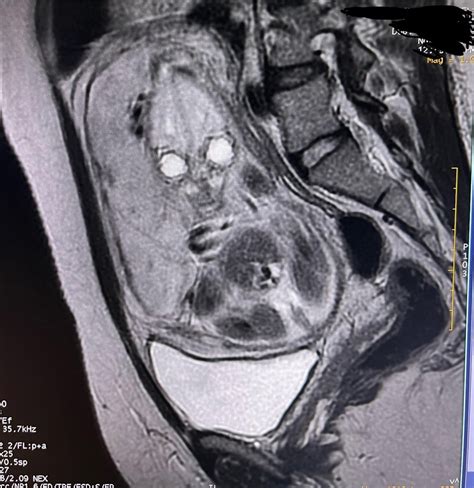

• Suspected Fetal Anomalies: MRI can provide detailed images of the fetus, helping to detect and diagnose congenital anomalies that may not be visible on ultrasound.

• Placental Abnormalities: MRI can help identify placental abnormalities, such as placenta previa or placental abruption, which can pose risks to both the mother and the fetus.

• Maternal Conditions: MRI can be used to diagnose and monitor maternal conditions that may affect pregnancy, such as pelvic pain, back pain, or neurological symptoms.